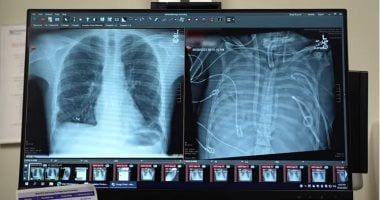

تمكن جراحون في مستشفى نورث وسترن ميديسن في شيكاغو، من إبقاء مريض في حالة حرجة على قيد الحياة لمدة 48 ساعة بعد إزالة كلتا رئتيه.

ووفقا لـ"Fox news"، فإن المريض، والذى يبلغ من العمر 33 عامًا ولم يتم الكشف عن اسمه، تم نقله جوًا في الأصل إلى مستشفى نورث وسترن التذكاري بسبب فشل رئوي مرتبط بعدوى الإنفلونزا في ربيع عام 2023، وعندما تفاقمت حالته إلى التهاب رئوي حاد وتسمم الدم، توقف قلبه وقام الفريق بإجراء الإنعاش القلبي الرئوي.

قام الفريق الطبي بتصميم "نظام الرئة الاصطناعية الكاملة (TAL) "، الذي تولى عملية تبادل الغازات (الأكسجة وإزالة ثاني أكسيد الكربون)، وحافظ على تدفق الدم إلى القلب على أمل أن يتمكن من إبقاء المريض على قيد الحياة بعد إزالة كلتا رئتيه المريضتين.